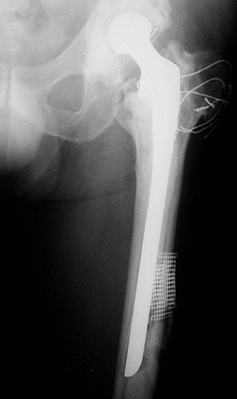

![]() |

Figure 106.9. Failure of a cemented revision with a long stem after 4 years.

become more common because of the poor results with cemented fixation.

Uncemented components can be proximally or fully porous coated.

Uncemented components require adequate living bone stock to be in

intimate contact with the prosthesis in a mechanically stable setting

so that bone ingrowth can occur. The implant must be rotationally and

axially stable at the time of implantation to maximize the opportunity

for biologic ingrowth.